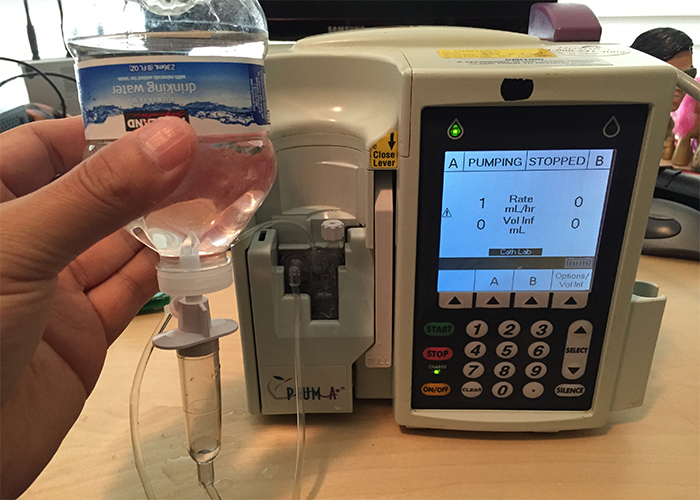

قیمت: 75٬581 تومان - دسته بندی فایل: علوم پزشکیدانلود پاورپوینت پمپ ها و کنترل کننده های سرم

عنوان پاورپوینت: دانلود پاورپوینت پمپ ها و کنترل کننده های سرمفرمت: پاورپوینت قابل ویرایشتعداد اسلاید: 81پاورپوینت کامل و آماده ارائهفهرست مطالب:مشخصات پمپ ها و کنترل کننده هاوسایل متفرقهروش های دیلاتاسیون وریدبی حسی موضعی قبل از سوزنروش های ورود به ...